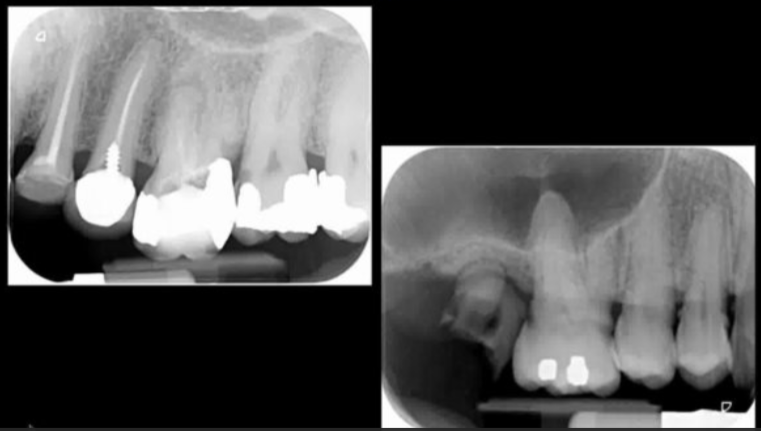

what is shown on this picture?

periacpical granuloma